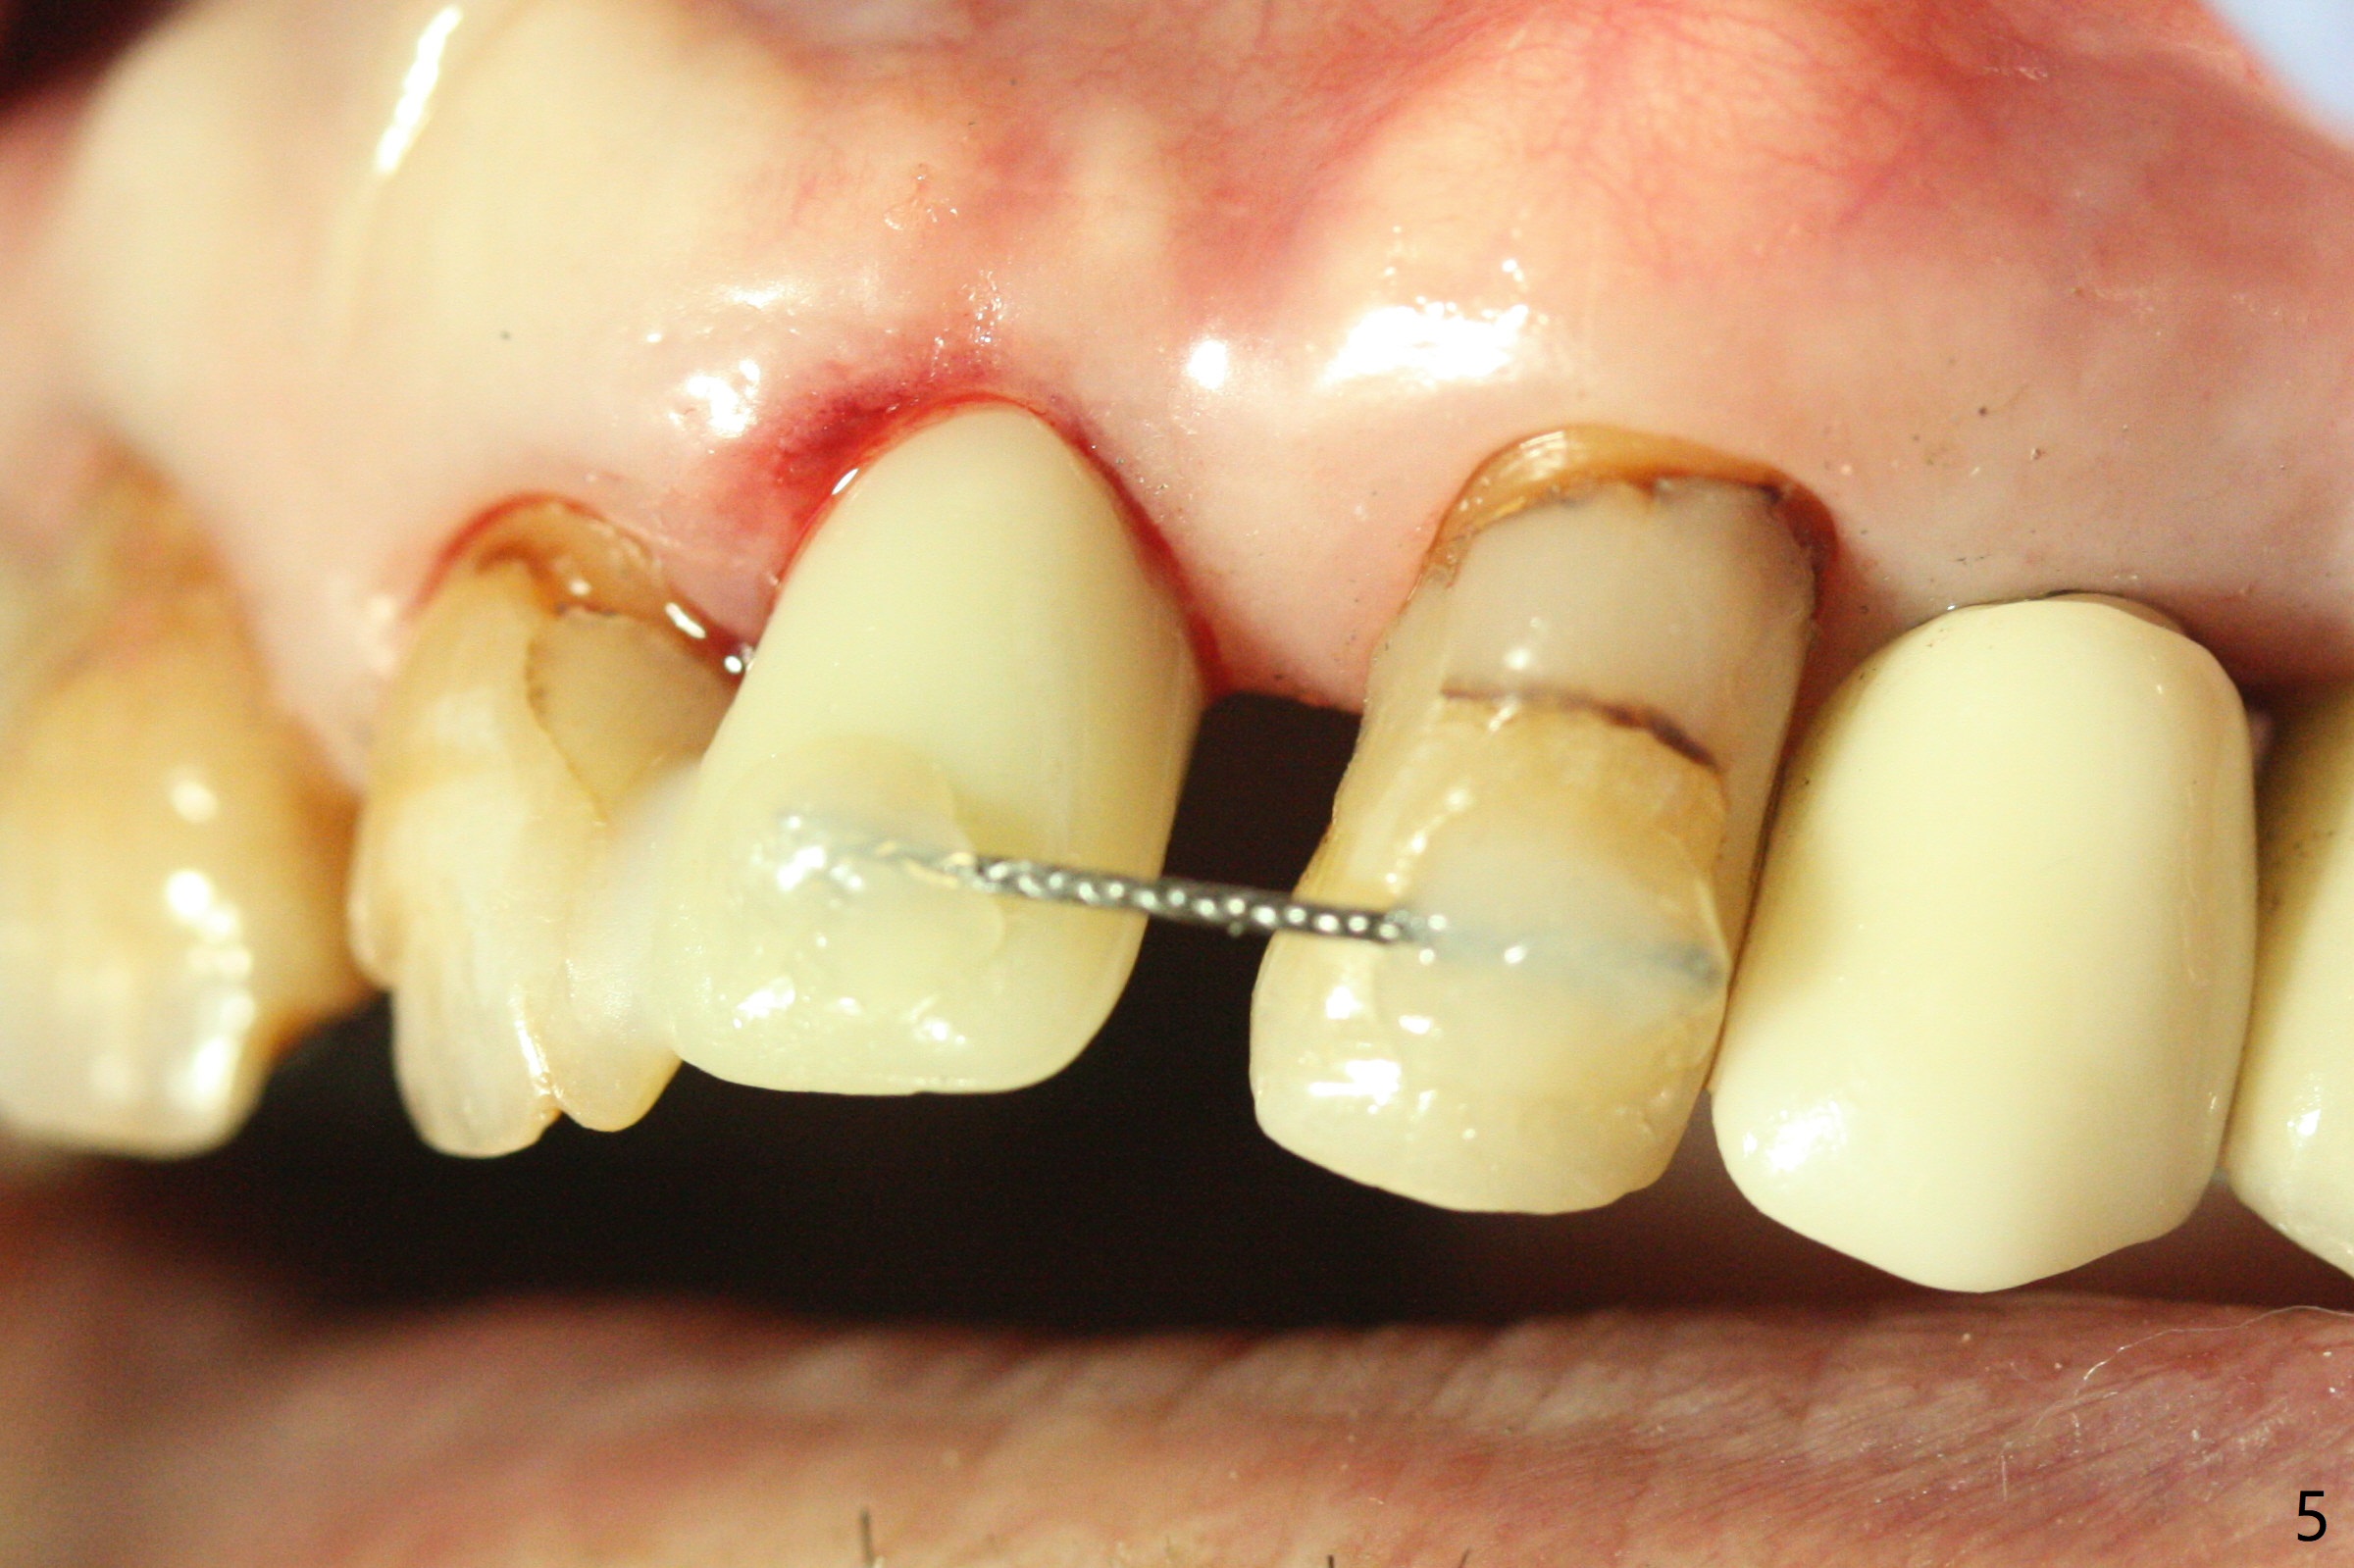

After undersized drilling in depth at #10 (2.2x13 mm (10.5 mm offset), Fig.1), a 2.5x13 mm 1-piece implant is placed (Fig.2,3), as compared to the design (Fig.3'). Following 3 more turns of the implant (~ 20 Ncm), bone graft and heavy buccal reduction of the coronal end of the abutment, an immediate provisional is bonded to the tooth #9 (Fig.4) and splinted to the tooth #11 with a twisted wire (Fig.5). To increase stability and reduce reduction, a 3 mm 1-piece implant could be used with 15 degree abutment. The implant remains stable 5 months postop (Fig.6). The implant seems to be flexible before heavy occlusal reduction; note the periimplant micro-space (Fig.7). The patient is a bruxer. The implant crown seems to be minimally mobile 2 months post cementation (Fig.8, without treatment). 牙冠粘固后1年1个月软硬组织正常(图九)。